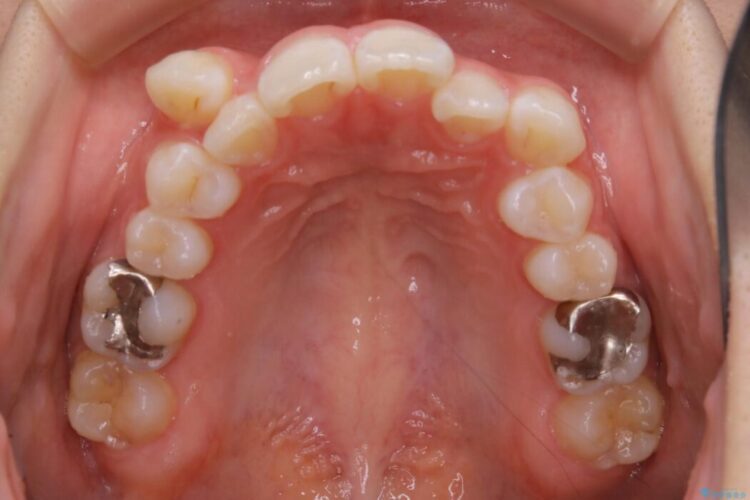

診査したところ叢生だけでなく生まれつき永久歯の欠損、いわゆる先天欠如により歯の本数が少ないため噛み合わせなどにも影響が出ている状態でした。

特殊な状況からの矯正治療となるため、抜歯する本数や位置、歯列を整えるにあたって必要なスペースの確保を慎重に計画し、インビザライン コンプリヘンシブパッケージでのマウスピース矯正を行いました。